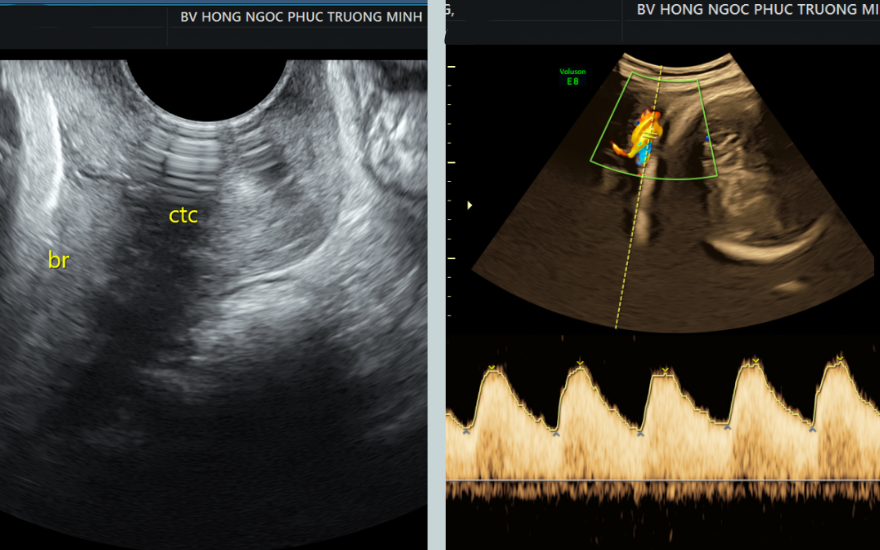

Hình ảnh siêu âm cho thấy bánh rau nằm sát lỗ cổ tử cung và dây rốn quấn cổ thai nhi.

Rau tiền đạo là hiện tượng rau thai che lấp một phần hoặc toàn bộ lỗ cổ tử cung, đường ra của em bé. Đây là 1 tai biến sản khoa có thể gây chảy máu bất thường trong thai kỳ và băng huyết trong quá trình chuyển dạ. Trong khi đó, dây rốn quấn cổ khi thai đã lớn có thể gây khó khăn cho quá trình di chuyển của thai nhi, từ đó dẫn đến hệ lụy đáng tiếc nếu không kịp thời xử lý.

“Do rau tiền đạo bám mép lại nằm ở mặt sau nên rất khó phát hiện nếu siêu âm không kỹ. Trường hợp này nếu để chuyển dạ tự nhiên có thể gây chảy máu ồ ạt, nguy cơ đe dọa tính mạng cả mẹ và con”, BSCKI Tống Thị Vân (Khoa Sản Phụ Khoa - BVĐK Hồng Ngọc) cho biết.